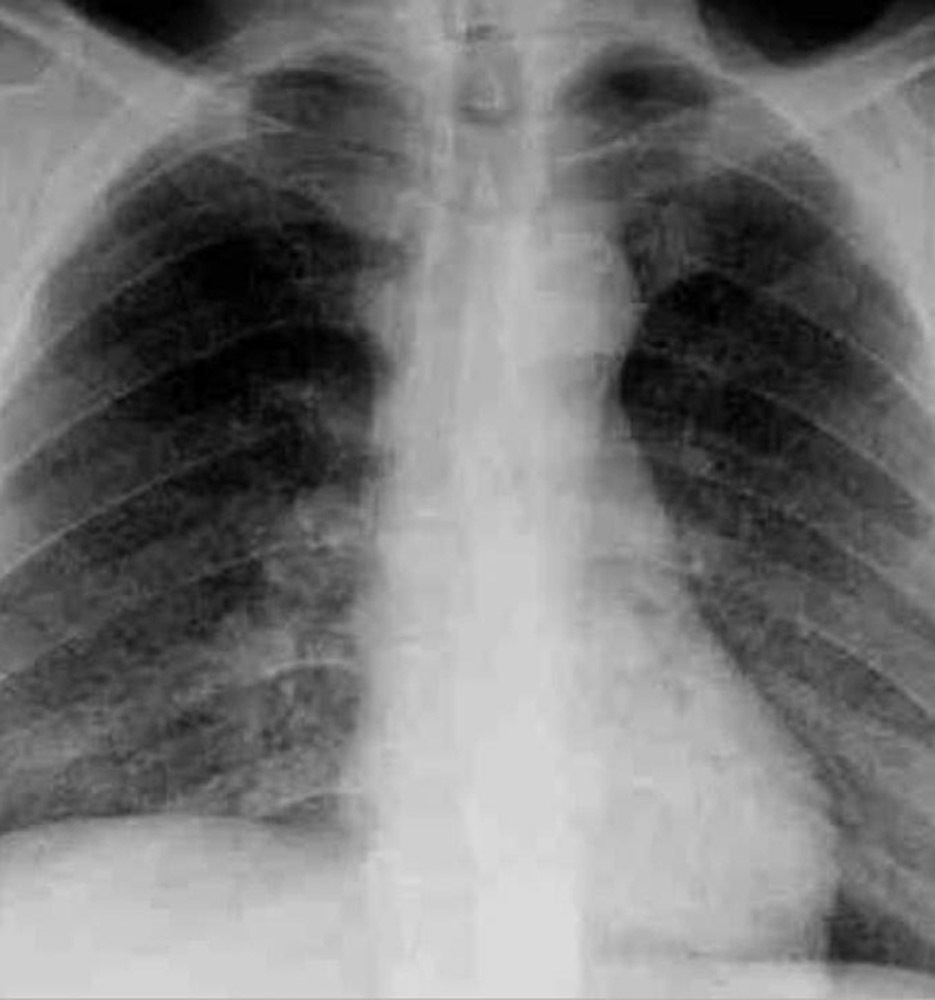

Il s’agit bien d’une miliaire tuberculeuse.